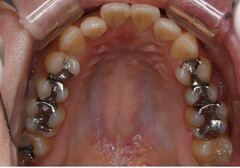

1・銀歯から始まる 歯を失う連鎖

成人のおよそ80%の方に、銀歯が口の中に入っています。

虫歯になる→歯を削る→型を取る→銀歯を入れる→虫歯が再発→大きく歯を削る→神経を抜く→

金属の土台を入れて銀歯を被せる→歯根破折を起こす→抜歯になる

私は決して銀歯を否定しているわけではありません。

適合の良い銀歯は、セラミックに比べ安価で、丈夫で、歯を削る量も少ないので、いい材料だと思います。

ただし、圧倒的に適合の悪い銀歯が多いのが実情ですけど。